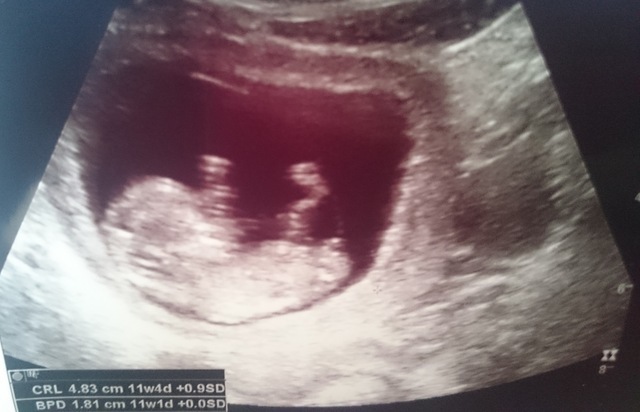

11週4日(11w4d・女の子)|misk さん(23歳)

エコー写真撮影時のエピソード:

妊娠した時、切迫流産と言われお腹の中でちゃんと育つかどうかもわからなかったけど、ちゃんとお腹の中で育ってくれてやっと人の形になった時のエコー写真。

病院に行く度不安で不安で仕方なかったけどこの時は本当にうれしかった。